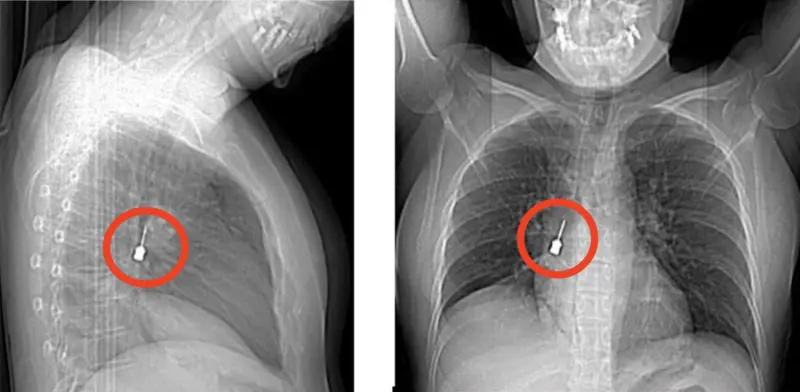

Una giovane donna si è presentata al Pronto Soccorso del Grande Ospedale Metropolitano (G.O.M.) di Reggio Calabria dopo giorni di tosse persistente e dolore intenso al petto. I medici, dopo aver visionato una Tomografia Computerizzata (un esame diagnostico di imaging medico che permette di ottenere immagini dettagliate dell’interno del corpo utilizzando raggi X e un computer), hanno fatto una scoperta sorprendente, un cacciavite odontoiatrico accidentalmente inalato era rimasto incastrato nel bronco lobare inferiore del polmone destro, provocando anche un pneumomediastino, ossia la presenza di aria nello spazio tra i due polmoni.

Vista la gravità della situazione, la donna è stata immediatamente ricoverata e trasferita in sala operatoria per un intervento broncoscopico d’urgenza. La delicata procedura è stata eseguita dal Direttore dell’UOC di Chirurgia Toracica, Baldassare Mondello, insieme alla sua équipe, che è riuscita a rimuovere il corpo estraneo metallico senza alcuna complicazione.